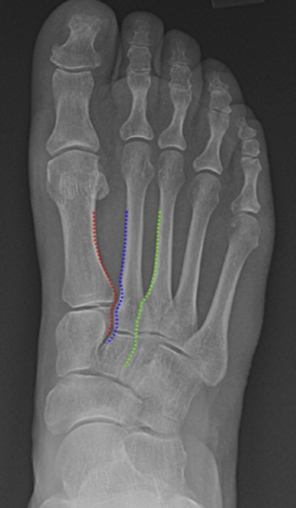

In the front view, the medial edges of M2-C2 (blue dotted line) and M3-C3 (green dotted line) must be aligned. The lateral edges of M1-C1 (red dotted line) should be aligned (Figure 13).

The gap between C1 and M2 should be less than 2 mm. The assessment of medial TMT joint line stability was described by Coss et al (28) using the abduction stress manoeuvre.